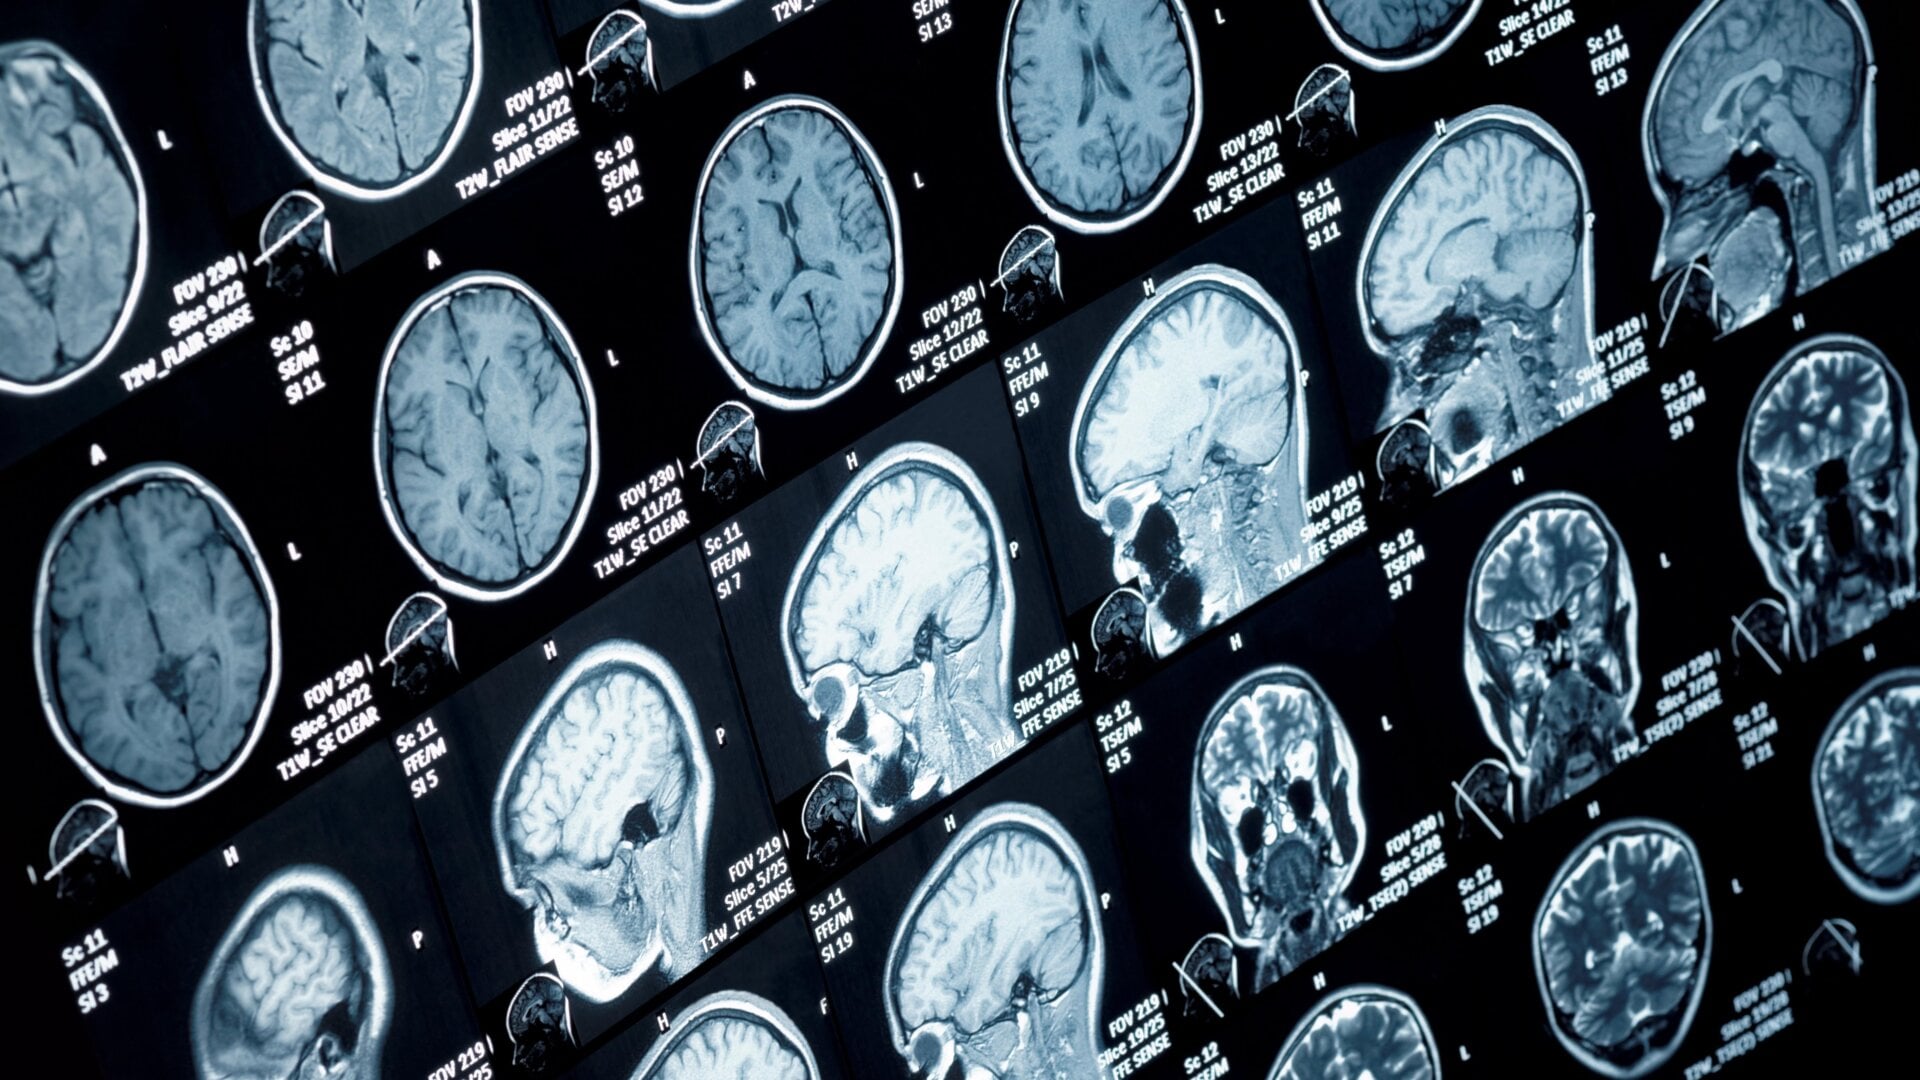

Dans une étude, les auteurs ont scanné le cerveau de 81 patients décrits comme ayant subi des « incidents de santé anormaux » à l’aide de l’IRM ; dans l’autre, L’équipe a effectué une large gamme de tests médicaux sur 86 personnes. Ces patients ont été comparés à des témoins correspondant en termes d’âge et d’autres caractéristiques. Dans l’ensemble, les chercheurs ont trouvé peu de différences entre les deux groupes.

« Dans cette étude exploratoire de neuroimagerie , il n’y avait aucune preuve significative détectable par l’IRM de lésion cérébrale parmi le groupe de participants qui ont incidents] par rapport à un groupe de participants au contrôle appariés », ont écrit les auteurs de l’étude IRM.